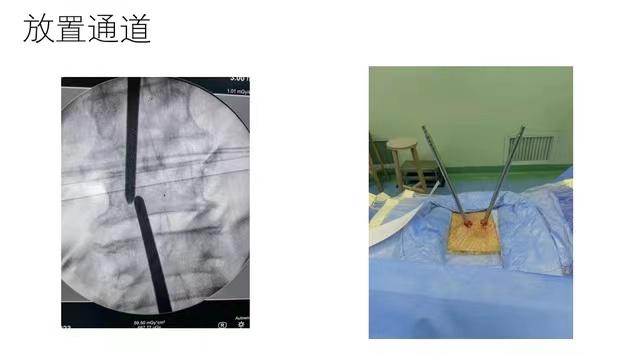

相對(duì)于常規(guī)手術(shù)方式,單邊雙通道內(nèi)鏡技術(shù)微創(chuàng)手術(shù)是一項(xiàng)新興的微創(chuàng)脊柱內(nèi)鏡技術(shù),通過建立兩個(gè)通道(一個(gè)觀察通道、一個(gè)操作通道)進(jìn)行手術(shù)操作,在內(nèi)鏡輔助下完成腰椎髓核摘除、椎管減壓、植骨融合等操作,由于是采用兩個(gè)通道,所以操作器械不受尺寸的限制。提供良好的照明,有利于助手的配合。通過手術(shù)內(nèi)窺鏡的放大作用,使手術(shù)也更加精確和安全。范純?nèi)┦拷榻B,UBE和椎間孔鏡都是脊柱內(nèi)鏡微創(chuàng)手術(shù),椎間孔鏡技術(shù)多用于治療單純腰椎間盤突出癥, UBE技術(shù)不同于椎間孔鏡技術(shù),除了常規(guī)腰椎間盤突出病例,尤其適用于復(fù)雜腰椎間盤突出、椎管狹窄、腰椎滑脫等復(fù)雜病例的內(nèi)鏡微創(chuàng)治療,該手術(shù)方式類似于傳統(tǒng)開放手術(shù),即屬于微創(chuàng)的手術(shù)方式,也能達(dá)到開放手術(shù)的治療效果,實(shí)現(xiàn)傳統(tǒng)開放手術(shù)的內(nèi)鏡化,最大程度減小對(duì)病人的創(chuàng)傷,有利于病人快速康復(fù)。近年來,漳州市中醫(yī)院骨傷科作為省內(nèi)骨傷專業(yè)唯一的國(guó)家臨床重點(diǎn)??疲剖乙恢敝铝τ诠强圃\療精準(zhǔn)化、微創(chuàng)化、智能化,同時(shí),不斷加強(qiáng)人才隊(duì)伍的建設(shè),通過引進(jìn)高端人才及團(tuán)隊(duì)進(jìn)行技術(shù)交流與指導(dǎo),帶動(dòng)學(xué)科建設(shè)。范純?nèi)t(yī)學(xué)博士就是醫(yī)院在引進(jìn)高端人才及團(tuán)隊(duì)工作的一個(gè)縮影。